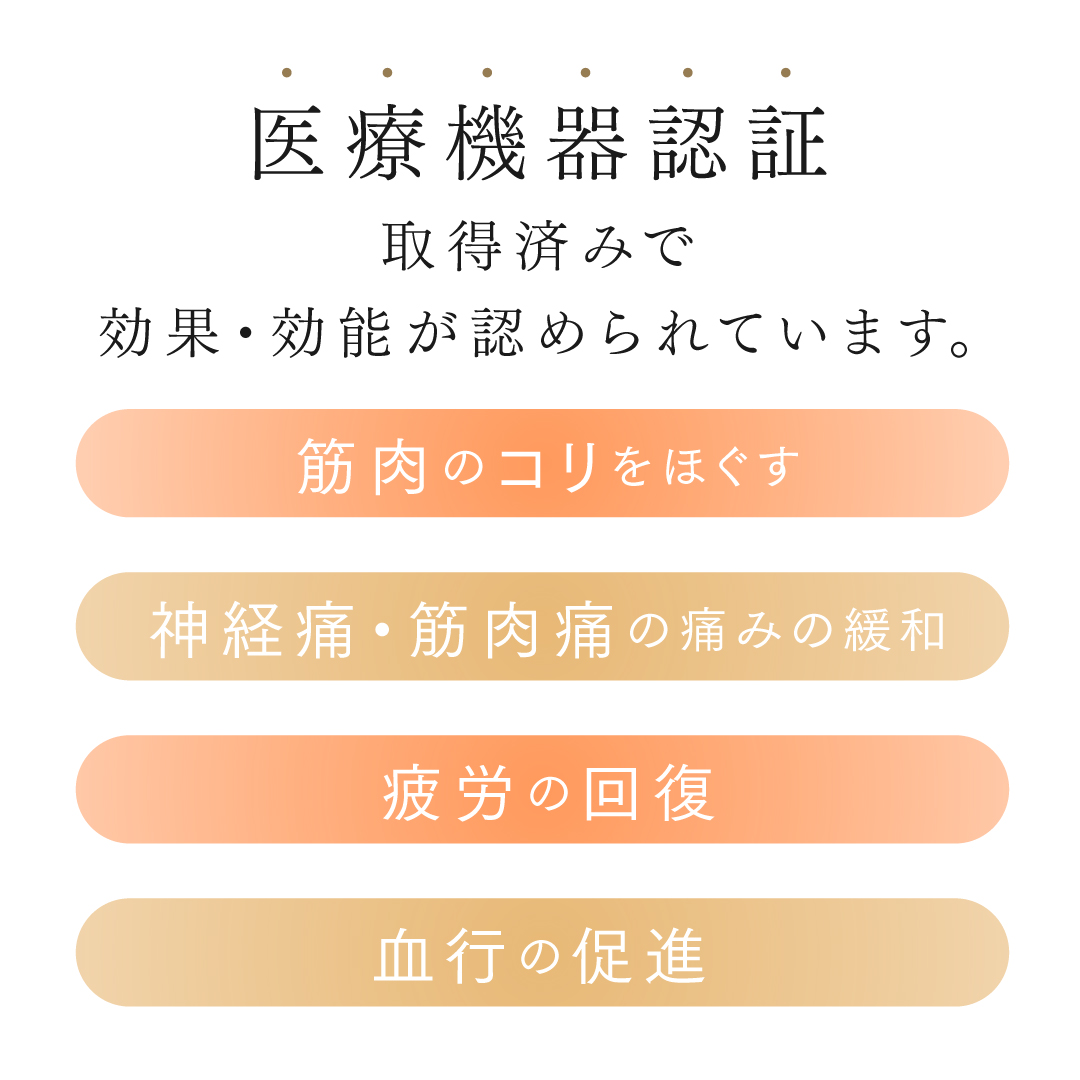

筋肉のコリをほぐす

神経痛・筋肉痛の痛みの緩和

疲労の回復

血行の促進

医療機器認証

取得済みで

効果・効能が認められています。